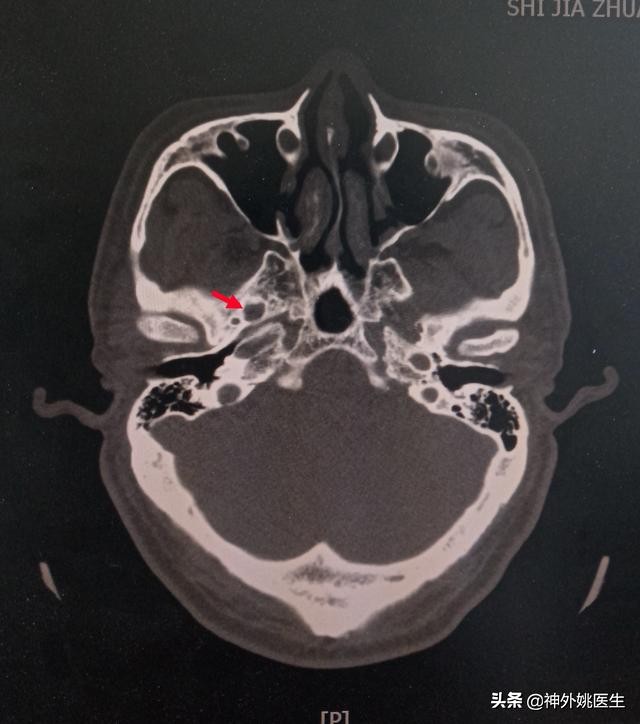

头CT检查:(图1、2)

图1 后颅窝未见占位性改变。

图2 卵圆孔形态规则,宽大(红色箭头所示)。